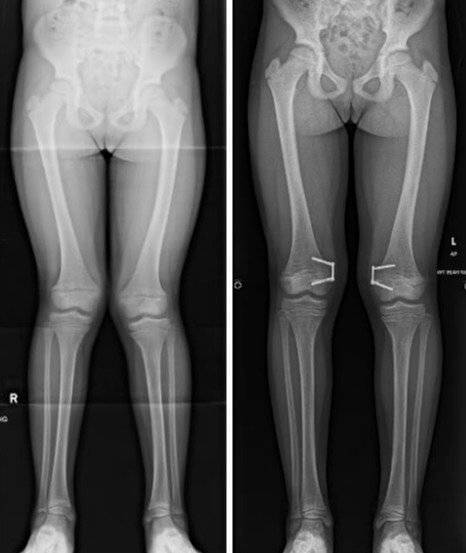

Stel je voor dat je honderden jaren geleden een gezondheidsprobleem had. Het beste wat je waarschijnlijk zou krijgen is een sessie bloedzuigers, of wat dierlijke urine om in te baden als je geluk had. Maar wat als je problemen had met je botgroei, zoals het kind op de foto's hier? Een geleide groei-operatie, zoals dit kind onderging, was ongehoord en ze zouden hun hele leven last hebben gehad van misvormde benen, wat hen onmiskenbaar pijn zou hebben gedaan.

Gelukkig is de geneeskunde in deze tijd geavanceerd genoeg om dit soort problemen te corrigeren, zoals de foto hier laat zien. Gelukkig voor dit kind mag het gelukkig en gezond opgroeien na het ondergaan van een corrigerende operatie.